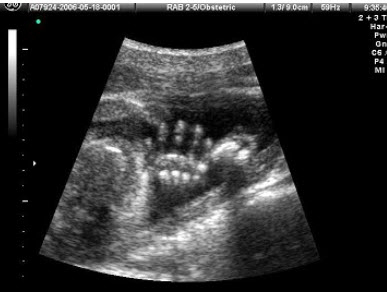

58、单项选择题

女性,26岁,停经29周,产前B超检查如图,超声诊断为()

A.胎盘早期剥离

B.正常中期妊娠

C.胎儿脐带绕颈

D.胎儿畸形,腹壁裂

E.畸胎瘤